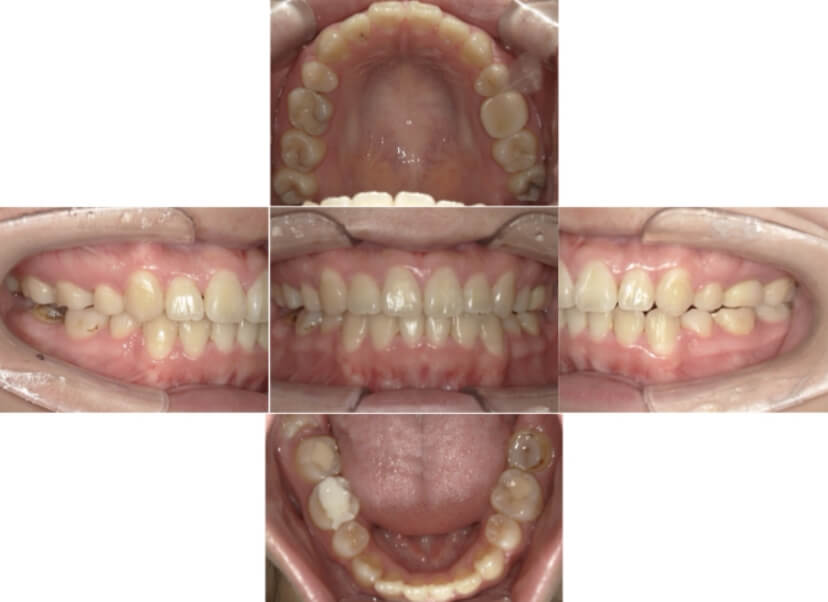

症例3

叢生

抜歯

ブラケット矯正

症例解説

上下顎叢生(上下の前歯のガタガタ)のケースです。

装置はラビアル(上下表側)で、上下顎の小臼歯を4本抜歯を行っています。抜歯したスペースを使って、上下の前歯の後方移動と叢生(ガタガタ)の改善を行っています。

主訴 八重歯を治したい。

年齢・性別 25歳 女性

お住まいの地域 神奈川県川崎市

治療方針 抜歯スペースを利用して上前歯の叢生(ガタガタ)の改善

抜歯部位 上下顎左右第一小臼歯

使用装置 ラビアル(上下表側)、顎間ゴム

治療期間 1年11か月

治療回数 16回

リテーナー クリアリテーナー

BEFORE